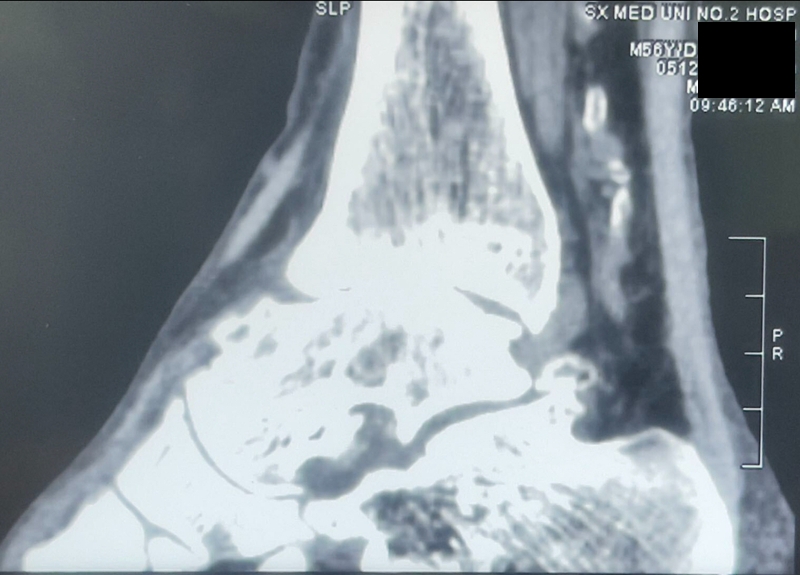

病例报告之二,xx,男,56岁,左踝创伤性关节炎。左踝崴伤6年,疼痛加剧3年。切口显露同前。

手术前资料

手术中资料